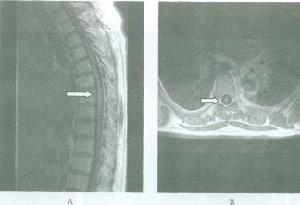

短頸畸形2.屈伸拉動力性頸椎側位片,融合椎體節段失去正常頸椎的圓滑曲線,椎間隙不發生變化。

3.短頸畸形在X線正側位片上很難清楚地顯示畸形部位,表現有以下幾點特徵:

①頸椎兩個或兩個以上椎體和附屬檔案的部分或全部融合。

②一個或多個椎間隙消失或部分消失。

③椎體扁而寬,有時為半椎體畸形。

④融合椎體的鄰近頸椎節段增生、退變。椎管矢狀徑減小形成椎管狹窄。

⑤可合併其他畸形。